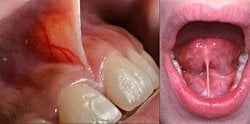

Dudak bağı (frenektomi) ne işe yarar ve evrimsel süreçte nasıl gelişmiştir?

diş eti ve dudak içi ete yapışık olan et parçası ve benzer bir şekil dilin altındaki dil bağı dilin hareketini kısıtlamasına rağmen neden hala var ve nasıl oluştu?